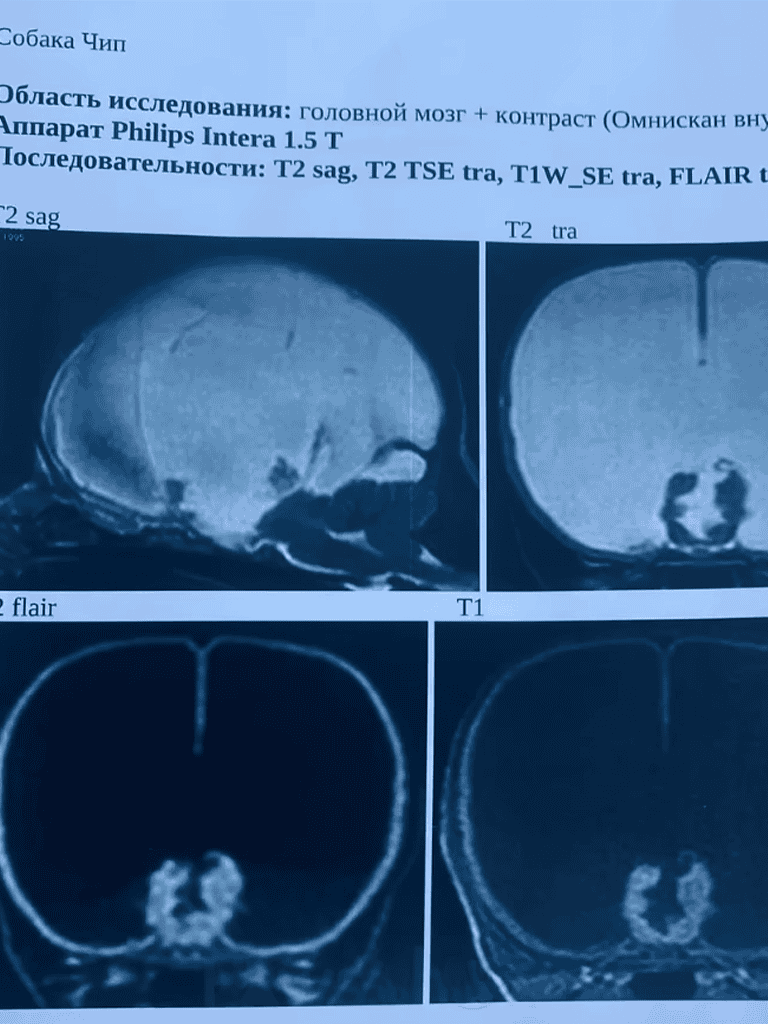

They found him trembling in a trash bin, wailing in agony. His swollen head suggested hydrocephalus.

The pup’s life was at risk. A medical exam was urgent, and surgery seemed the only hope.

An MRI was crucial, and I hoped the neurologist could provide guidance to help save his life.

‘You can’t fix what isn’t there,’ the doctor said. ‘He has no brain.’

Each day, fluid builds in Chipa’s head, and his body struggles more against the pain.

The doctor explained that fluid in his skull might be halting brain development.

While uncertain, intervention could ease his suffering and offer a chance at life.

Chipa had an appointment with a neurologist with surgery being likely.